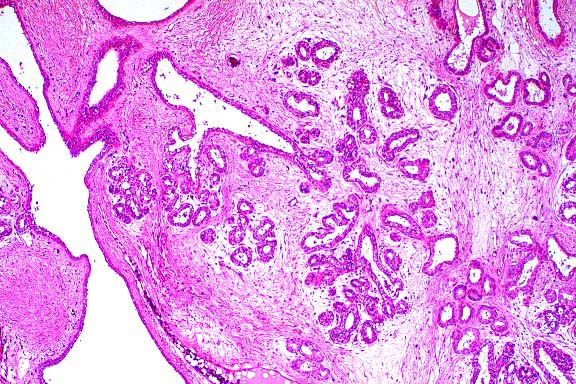

- Case 19-2. Thymus. There is diffuse, marked depletion

of lymphocytes and no distinction between cortical and medullary

zones. Reticular stromal cells remain with few small lymphocytes.

- AFIP Diagnoses:

- 1. Thymus and lymph node: Hypoplasia, lymphoid, diffuse,

severe, Jack Russell terrier, canine.

- 2. Thymus and lymph node: Extramedullary hematopoiesis, diffuse,

mild to moderate.

- Conference Note: Due to section variation, some slides

may contain only lymph node and no thymus. In the affected thymus,

there is marked decrease in size of thymic lobules, loss of demarcation

between the cortex and medulla, and prominence of medullary epithelial

reticular cells due to marked depletion of lymphocytes. In lymph

node sections, there is marked depletion of lymphocytes, with

virtual absence of paracortical lymphoid cells. Immunohistochemical

staining for CD3, a pantropic T-lymphocyte marker, performed

at the AFIP demonstrated diffuse marked decrease of CD3-positive

cells as compared with the thymus of the age-matched control

littermate, especially within the medulla where mature T-cells

are found. Small numbers of CD3-positive T-cells are present

in the cortex (immature T-lymphocytes).